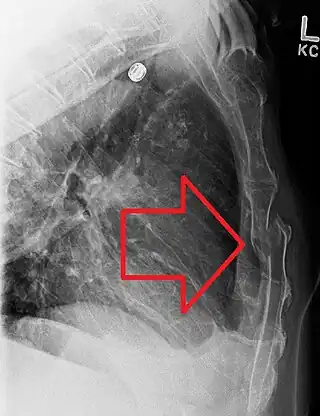

Fractura de esternón

La fractura de esternón es una deformación o falta de continuidad lineal del esternón, originado por fuerzas que exceden a la resistencia final del material que forma el hueso. Lo más frecuente es que se produzcan por traumatismo o por accidentes.[1] Estas fracturas son graves porque suelen implicar traumatismo cardíaco. Pueden provocar inestabilidad de la pared torácica y requerir fijación.[2]

En el diagnóstico se pueden utilizar las manifestaciones clínicas de una fractura, que incluyen: dolor, tumefacción, deformación, equimosis, inestabilidad y crepitación. Para confirmar el diagnóstico, se utilizan dos radiografías en distintos ángulos y TAC ( tomografía axial computarizada ).[5]